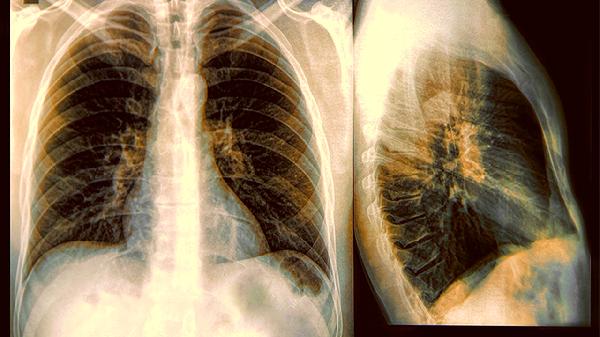

肺结节长在这6个位置,恶性概率大大增加,若发现快去医院检查

1.右肺上叶尖段

老烟民们的"重灾区",烟囱效应让有害物质更容易沉积在这个"阁楼"位置。这里的结节恶性比例比其他区域明显偏高。

三、贴近胸膜的潜伏者

1.脏层胸膜下结节